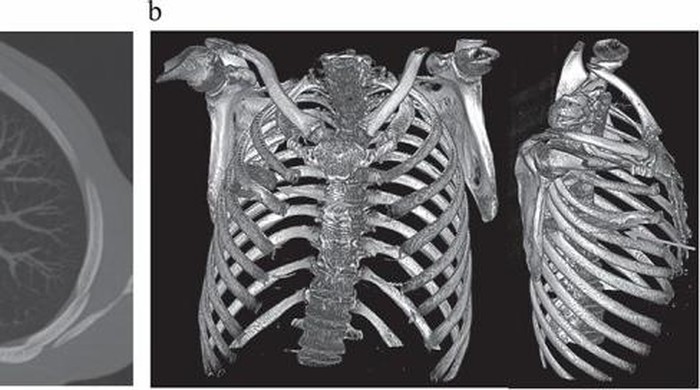

“Pencitraan awal dengan radiografi dada lateral menunjukkan adanya benda logam yang tertahan di bagian tengah toraks, dengan kekeruhan di sekitarnya yang kemungkinan merupakan hematoma terlokalisasi kronis atau yang sudah sembuh, atau fibrosis pascatrauma, yang merupakan sekuel dari luka tusuk pasien,” tulis para dokter. (Foto: Journal of Surgical Case Reports).

Saat perkelahian itu terjadi delapan tahun lalu, rumah sakit tempat ia dirawat tidak memiliki fasilitas radiologi. Karena setelah lukanya sembuh ia tidak lagi mengeluh sakit, tidak ada pemeriksaan lanjutan yang dilakukan. Adapun Nanah yang keluar ternyata merupakan akibat dari penumpukan jaringan mati di sekitar benda asing tersebut. (Foto: Journal of Surgical Case Reports).